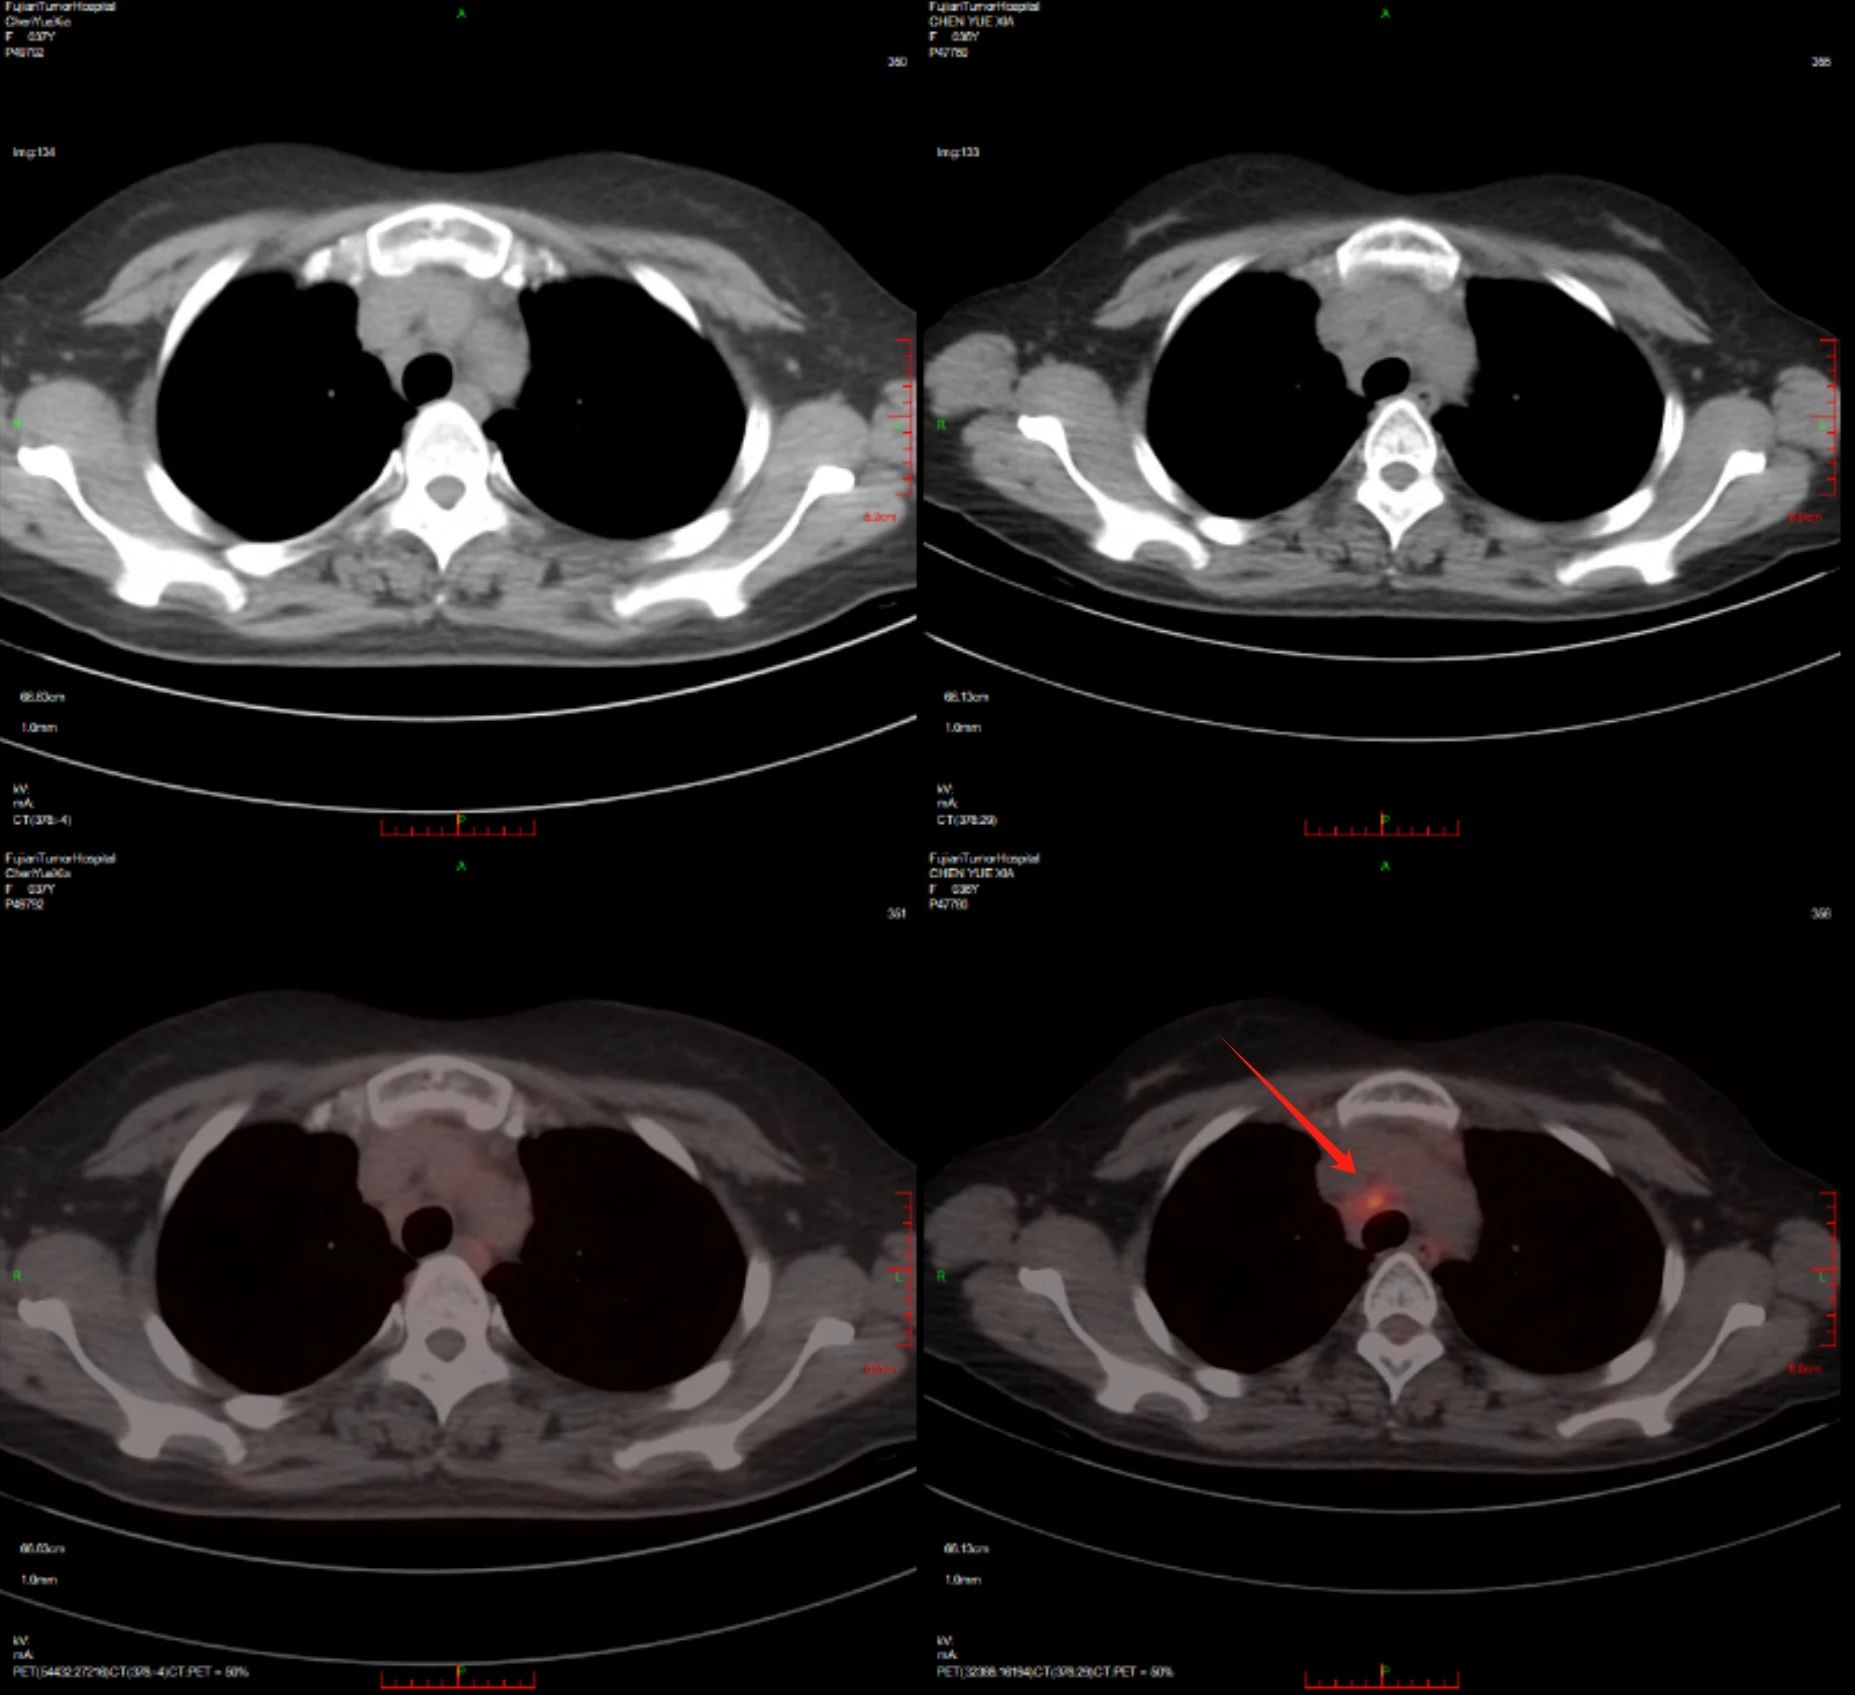

治疗后

治疗前

明确诊断后,团队仔细钻研病情,同时大量查阅最新文献指南。先是尝试免疫加靶向治疗(PD1单抗联合维布妥昔单抗),后又启用维布妥昔单抗联合苯达莫司汀方案,四个周期后患者达到完全缓解。接着,团队为患者实施自体干细胞移植治疗,并参考前沿文献开展靶向维持以巩固效果。近期随访显示,患者仍处于完全缓解状态,病情得到长期有效管控。